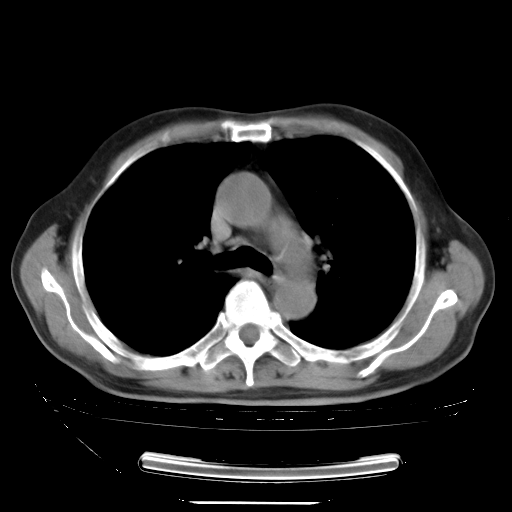

胸腹部CT,诊断意见:左上肺叶钙化灶、左侧胸膜局限性增厚并钙化、胆囊炎。描述部分肺组织呈磨玻璃样改变。